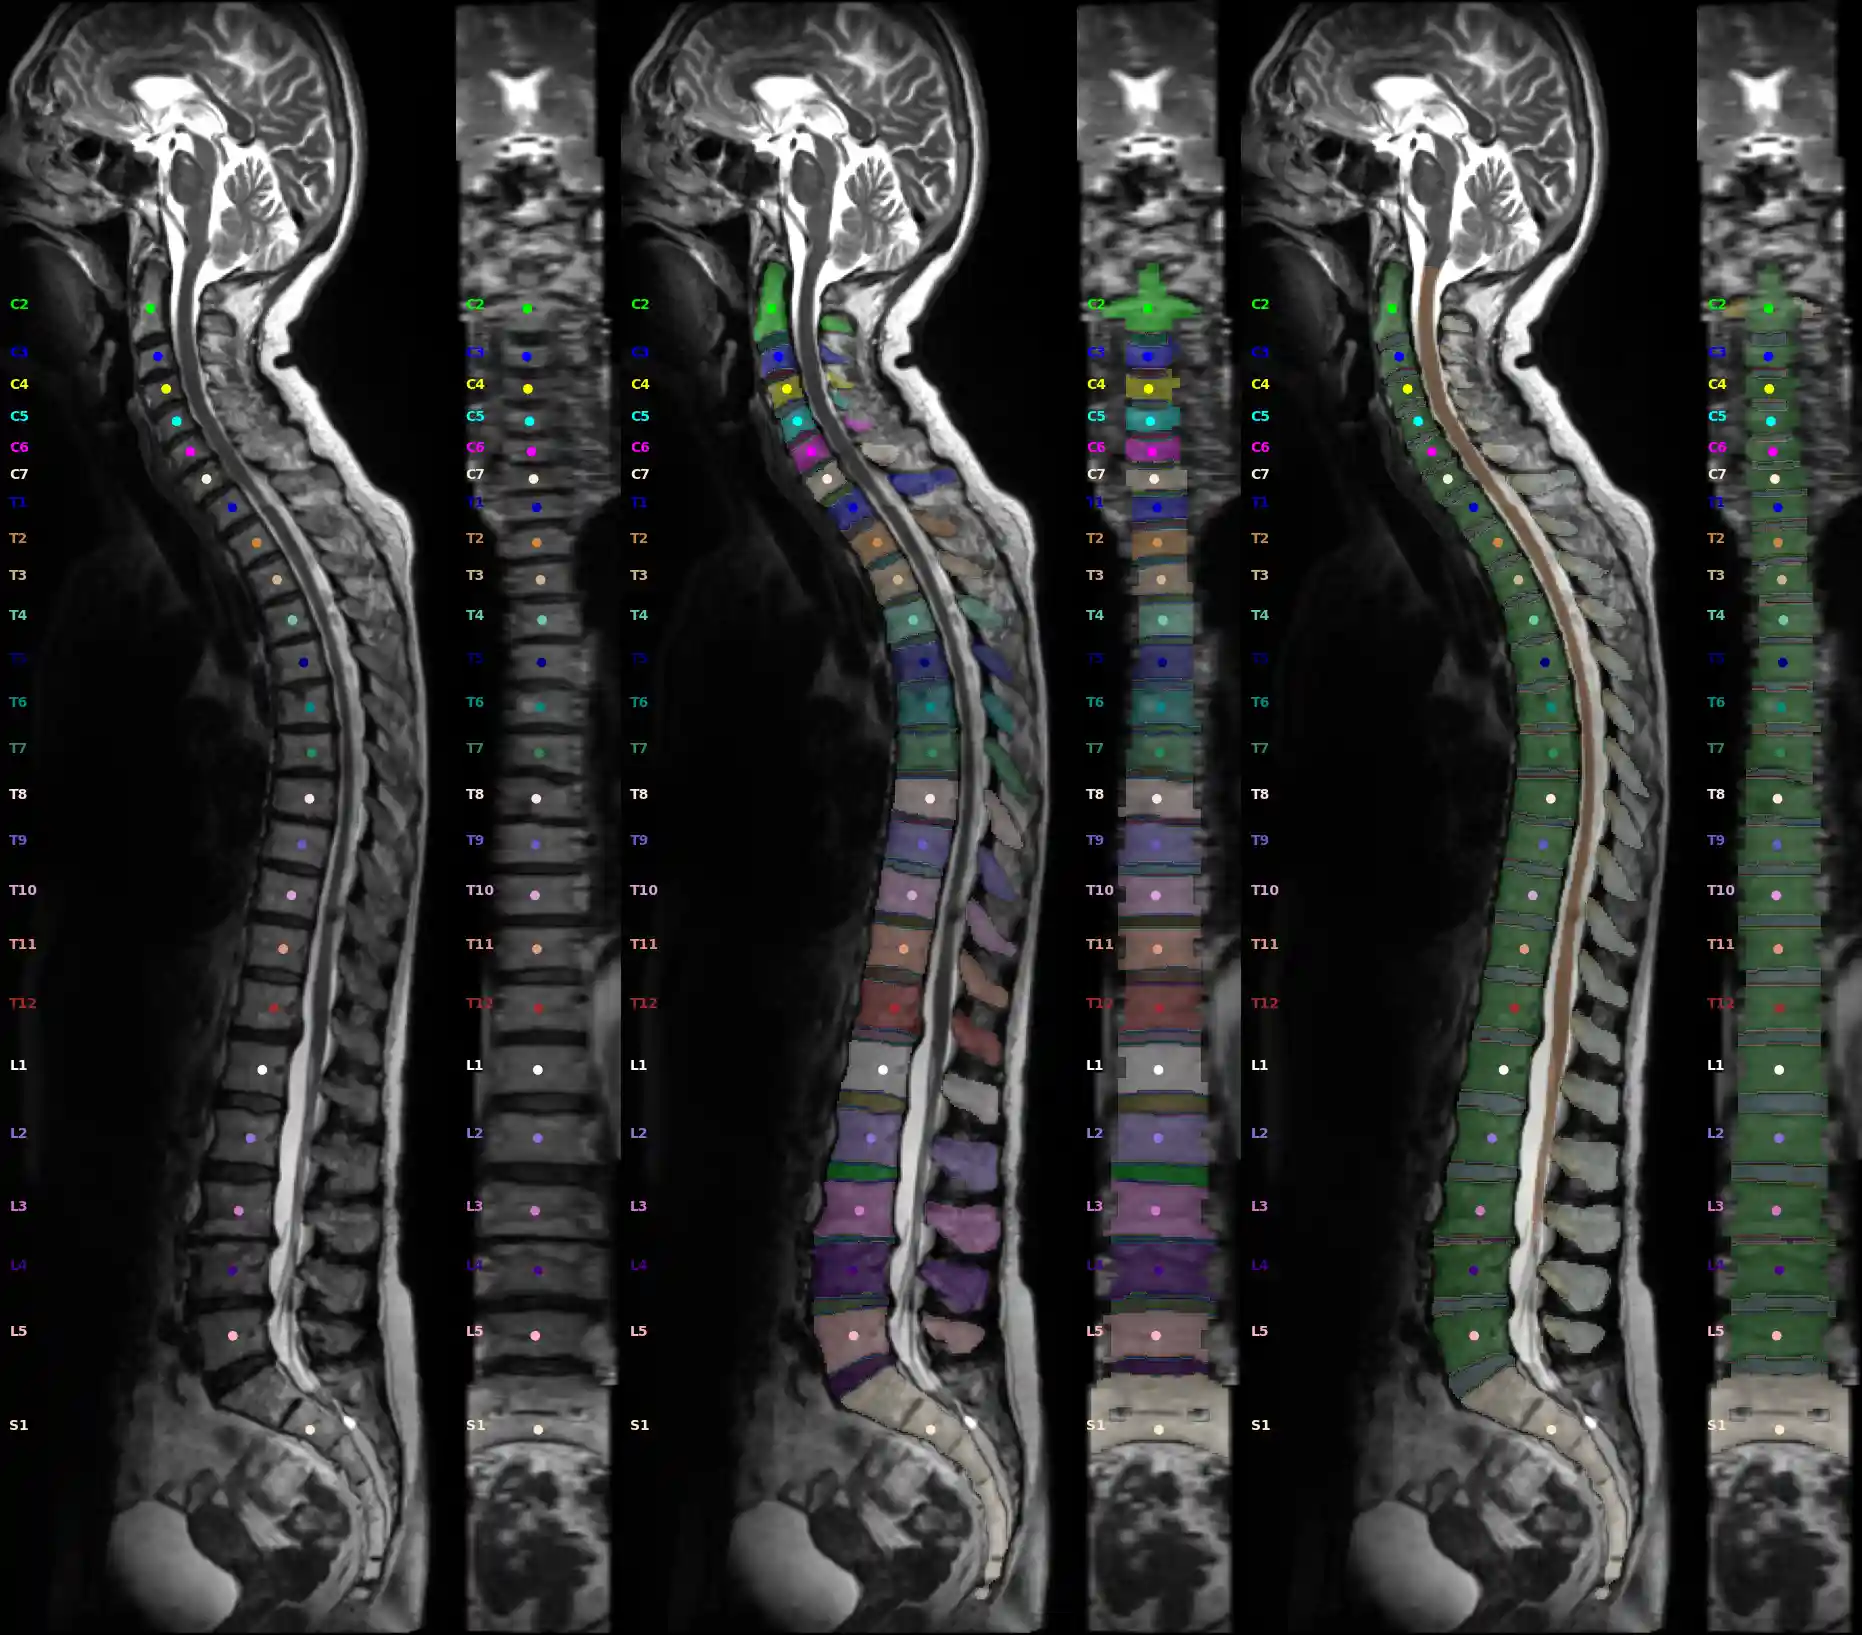

Image Source: Rule-based Key-Point Extraction for MR-Guided Biomechanical Digital Twins of the Spine;

SPINEPS will produce two mask: instance and semantic labels. With these we can compute our POIs. There are either center of mass points or surface points with bioloical meaning. See Validation of a Patient-Specific Musculoskeletal Model for Lumbar Load Estimation Generated by an Automated Pipeline From Whole Body CT